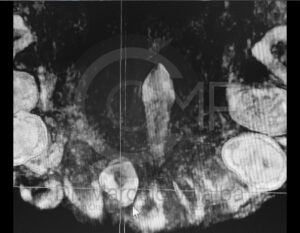

Antes de la extracción se realiza una valoración clínica y estudios de imagen, como radiografías panorámicas o tomografías, para conocer la posición del tercer molar, su relación con los nervios y planificar un procedimiento seguro y adecuado para cada paciente.

No es recomendable. Antes de extraer terceros molares es necesario realizar una valoración clínica y estudios de imagen para conocer la posición del diente, su relación con los nervios y el tipo de procedimiento más seguro para cada paciente.